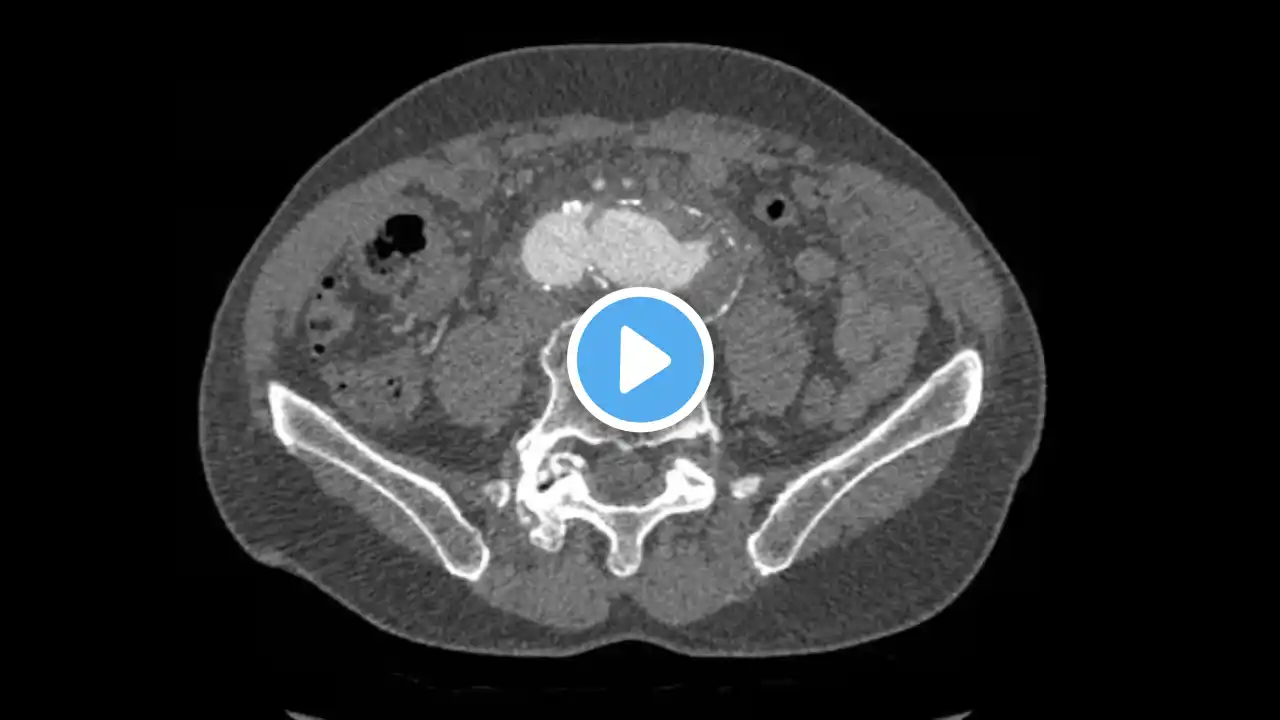

Amen A, et al. An Unusual Case of Hematemesis. JETem 2018. 3(4):V32-34. https://doi.org/10.5072/FK2RB7493D History of present illness: A 68-year-old female presented with back pain described as burning in her mid to upper back radiating to her chest with nausea and vomiting for several hours, which progressed to active hematemesis. Her vitals were significant for hypertension (160/95) and bradycardia (57). Her exam was notable for diminished breath sounds in the bilateral bases with rhonchi in the left lung base, and epigastric tenderness without rebound or guarding. A portable X-ray followed by a computed tomography (CT) angiogram of the chest and abdomen were ordered. Upon return from CT, the patient developed hypotension, worsening bradycardia, and altered mentation. Significant findings: The patient’s chest X-ray revealed a prominent mediastinum and opacification in the left middle and lower lung fields. The CT showed an aortic aneurysm extending from the thorax to the abdomen with rupture near T7 (blue arrow). It also showed periaortic hemorrhage with active extravasation (green arrow) likely secondary to a penetrating ulcer and bilateral pulmonary opacities concerning for hemothorax (pink arrow). Discussion: Thoracic aortic aneurysm (TAA) is a progressive and potentially deadly disease with a poor prognosis when left untreated.[1] Most TAAs are asymptomatic and may be detected incidentally on imaging. Although presentation can vary, chest or back pain might be the first presenting symptom and can represent rapid expansion, acute dissection, or rupture.[2] In the acute setting, chest X-ray might be the first imaging study performed during the initial evaluation of a patient with symptoms that suggest a potential for aortic disease. Predictive sensitivity of a widened mediastinum or abnormal aortic contour can be around 64% and 71% respectively, but the sensitivity of CXR is not adequate to definitively rule out acute aortic disease.[3] CT with contrast remains the imaging study of choice for diagnosis of acute thoracic aortic disease; it can be nearly 100% sensitive and can also demonstrate the presence of a dissection flap or rupture.[3] Overall mortality for ruptured TAA is 97%-100%.[4] While mortality is also high for repair of symptomatic TAA, repair is recommended for all symptomatic TAA (ruptured, associated with dissection, or causing pain).[2] However, surgery may not be indicated based on patient comorbidities, or clinical picture. Preemptive repair of asymptomatic TAA can eliminate the risk of rupture, which is primarily predicted by size.[5] Overall mortality for elective repair is 4.5% (4.6% for open repair and 3.6% for endovascular repair).[6] Current guidelines suggest surgical intervention when the risk of rupture-related complications exceed the risk of surgery-related complications, which is generally around a size of 5.5 cm. However, it is also dependent on the presence of genetic risk factors for dissection and rupture, exact location, and rate of aneurysm expansion.[3] In this case, cardiothoracic surgery determined that surgery would not confer any increased chance of survival based on the patient’s clinical condition, the size and location of the rupture, and the growing periaortic hemorrhage. The family decided to provide comfort measures only and the patient expired approximately one hour after presentation to the emergency department. For references or to download this video for teaching go to http://jetem.org/hematemesis/